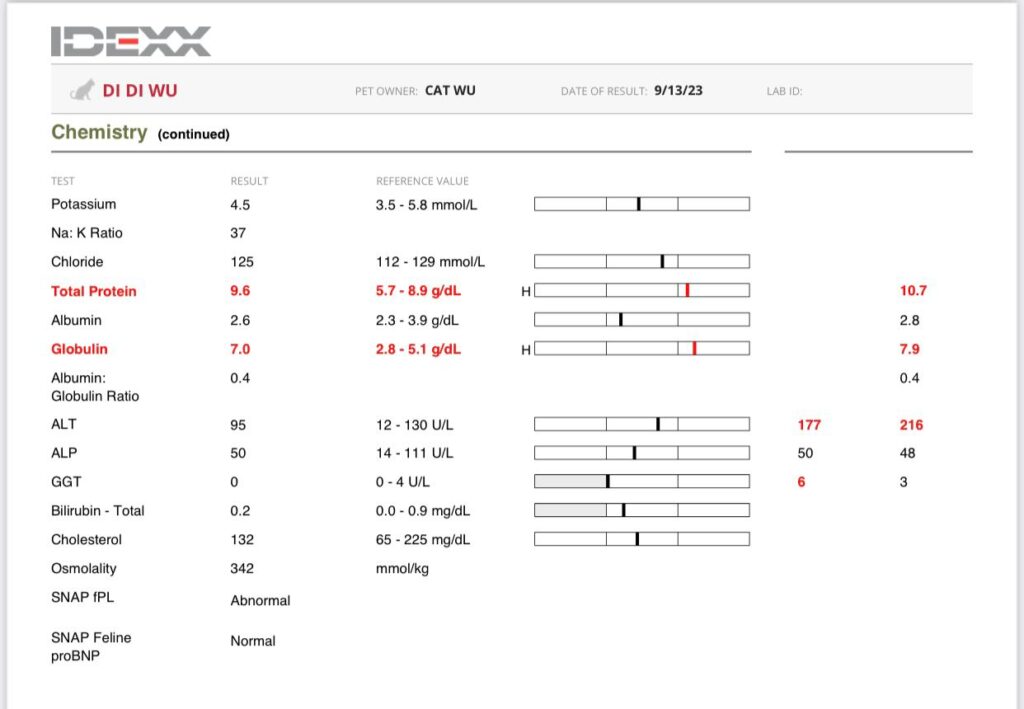

3.49kg – drop 180g in 4 days. V drastic weight change.

To taken Cbc, Chem 15, lytes, probnp, pancreatitis.

Results: probnp normal. So mur mur due to anemic?

Pancreatitis abnormal, sigh can’t send out for quantatitis cos no more bloods at clinic. Kns siak. Told clinic send out rena blood as didi for the quantative test. – confirmed

Didi slight high on glucose. Should be stress.

anemic for sure. HCT 21% plus I’ll start him on darbepoetin for sure too. Now is he needs ab? Waiting for dr nally to send summary.

For now is whack fluid, b12, Cerenia n bupre?

I rushed back 猫房 so today skip Subcut. tmr have to make a trip back, see how. Ursofalk can stop cos his GGT 0.

I was worried about didi extreme high retic: “Re Didi – internal bleeding less likely as BUN is still normal and no black poo noticed? More of something else infectious/inflammation going on – mouth/nose/UTI?/pancreatits/neoplasia. The CREA was high end normal it may be higher as he is very skinny”